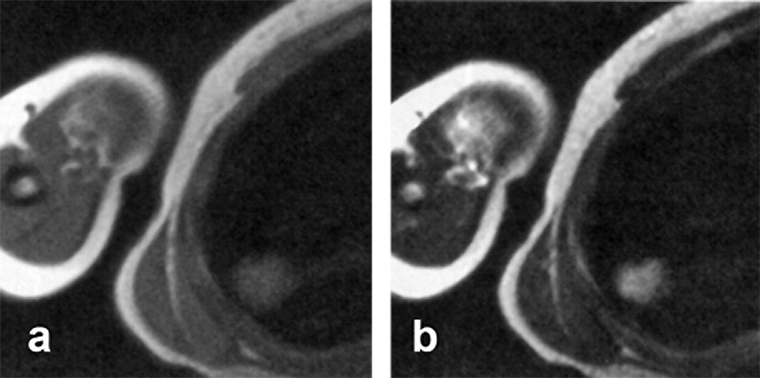

Figura 17-03:

(a) Transverse intermediately, and (b) T2-weighted images depict an ill-defined high signal in­­ten­­si­­ty le­sion in the right lung. Follow-up studies on another day and the use of CT did not show such a lesion. The cause of the artifact remained unclear.